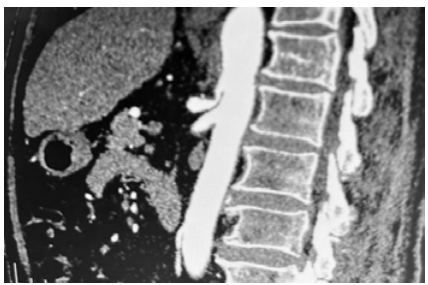

Uma paciente de 48 anos de idade compareceu ao pronto atendimento com dor abdominal epigástrica, que piorou no período pós-prandial, há aproximadamente 12 meses. Ela relatou ter procurado atendimento por múltiplas vezes, sem elucidação adequada do quadro. Já foi realizada a colecistectomia, sem indícios de melhora. Houve perda de 10 kg nos últimos 3 meses devido a esse quadro. Relatou piora da dor nos últimos dias, o que a fez procurar o atendimento de urgência. A paciente estava em bom estado, lactato 0,9. Exames cardiológicos estavam normais. Foi realizada angiotomografia, que evidenciou a imagem a seguir.

Enunciado 4079244-1

Com base nessa situação hipotética e na imagem acima, assinale a alternativa que apresenta o diagnóstico e a conduta adequados para o caso.